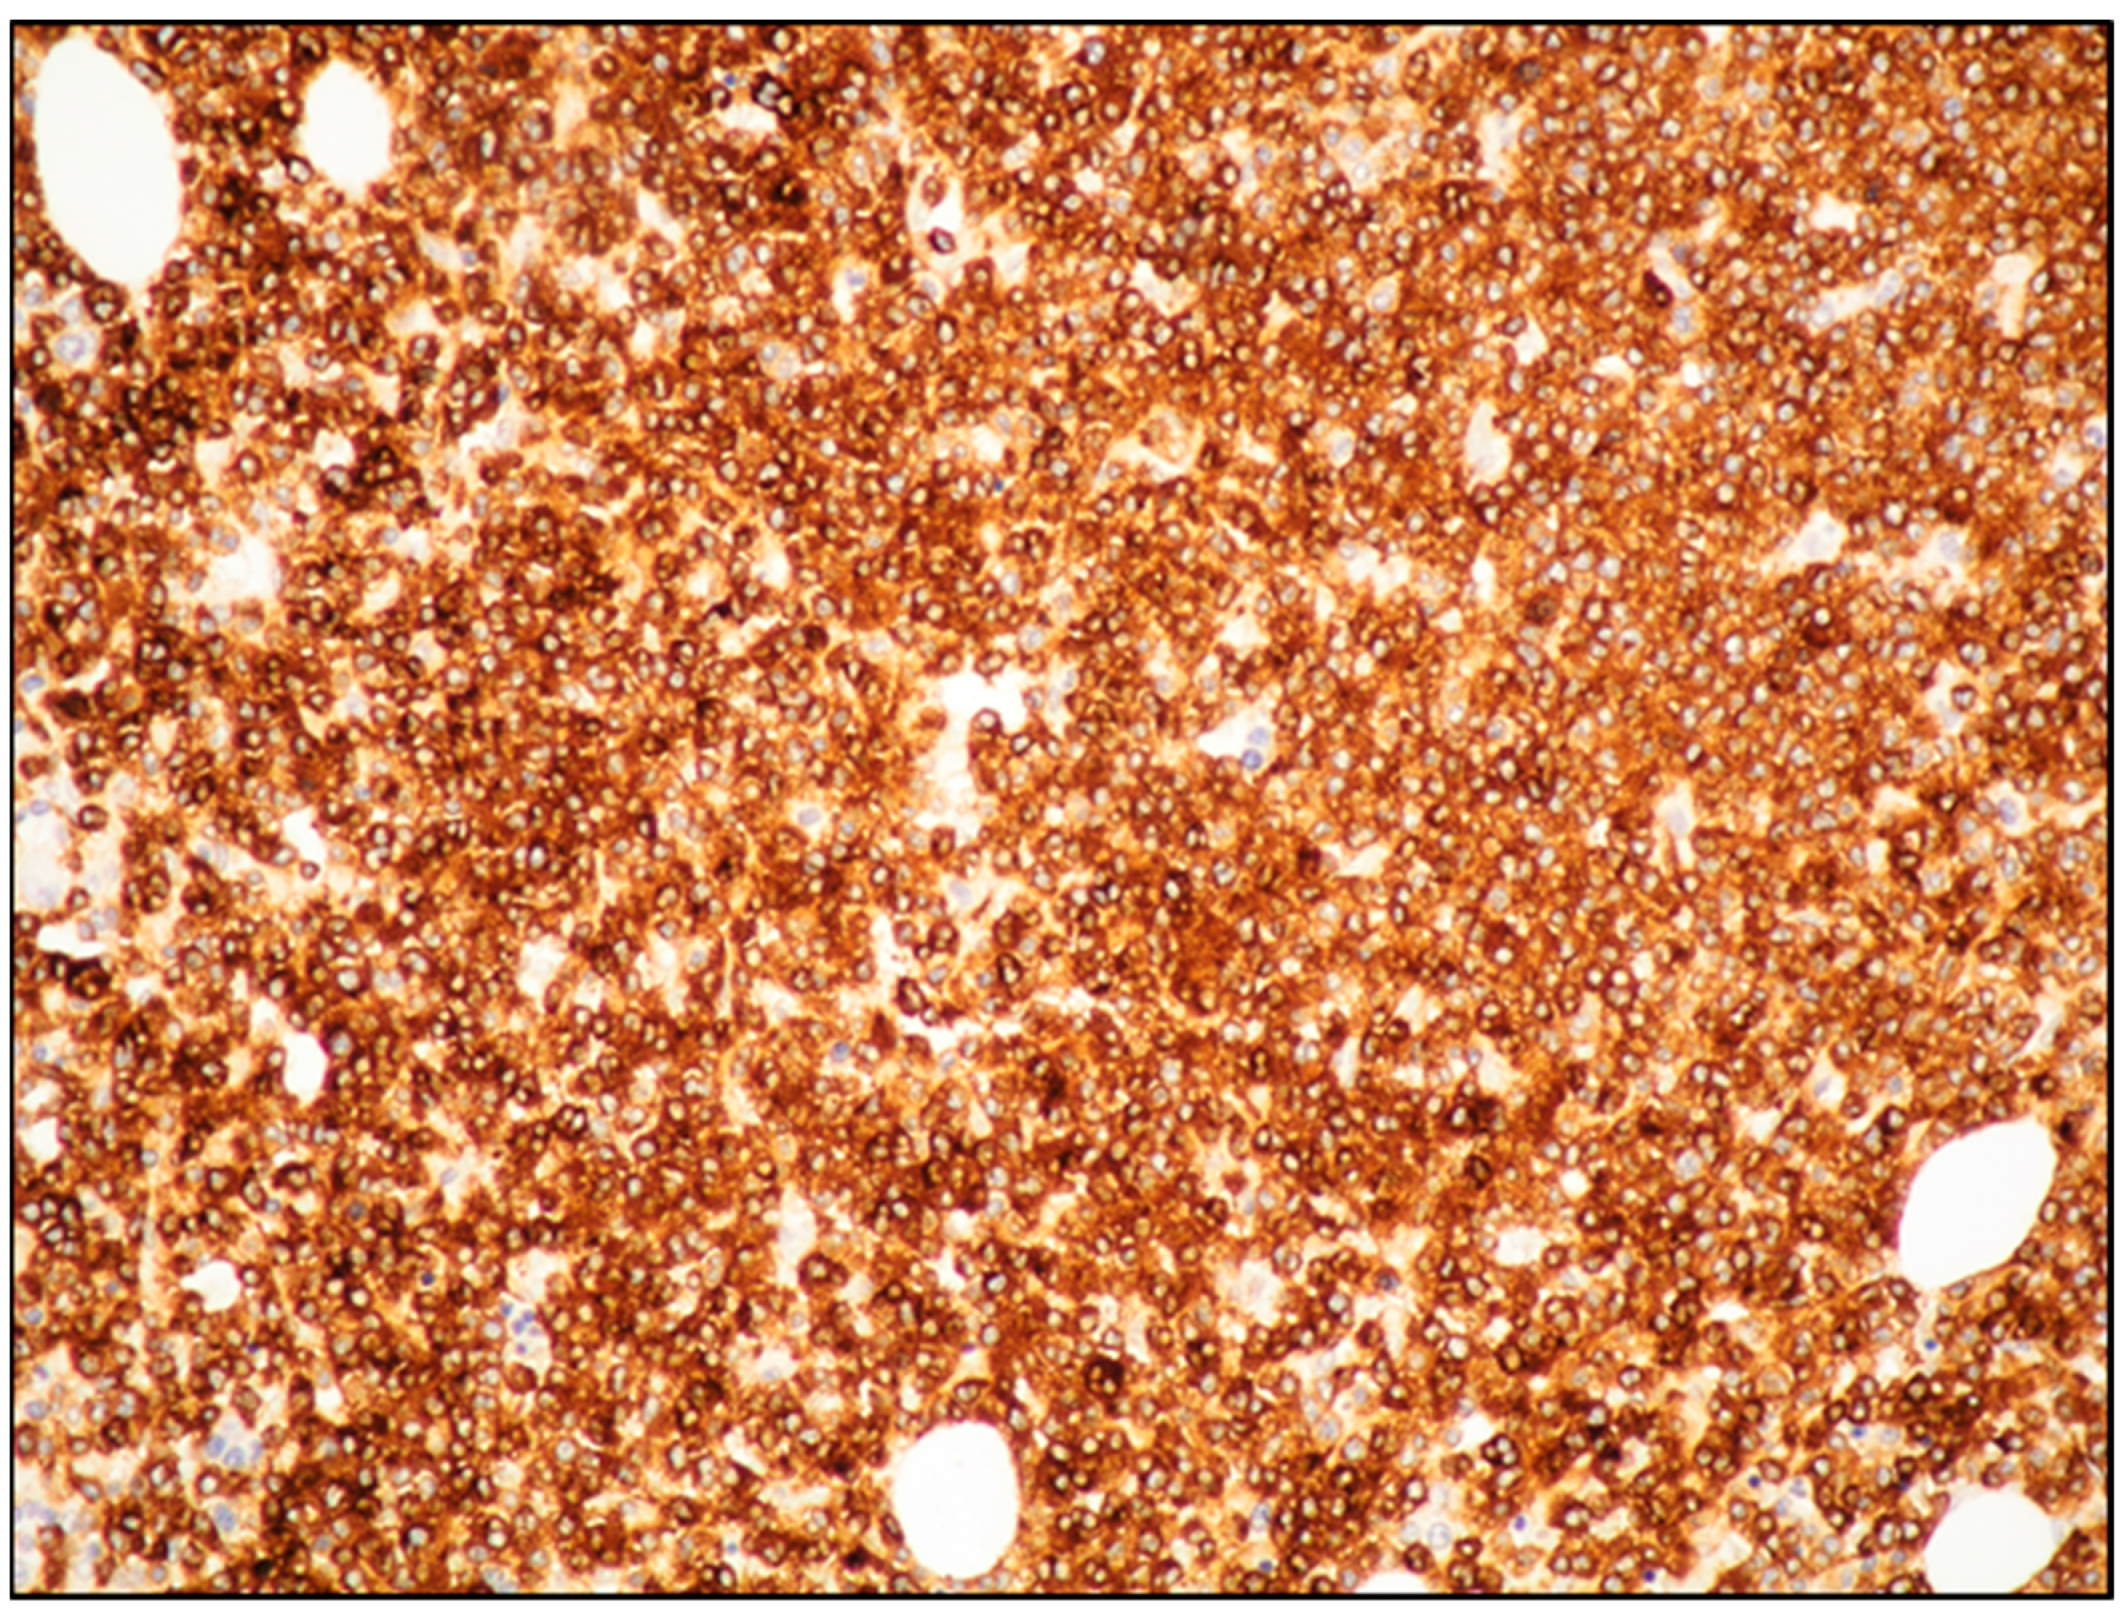

7. MCL: Immunophenotyping